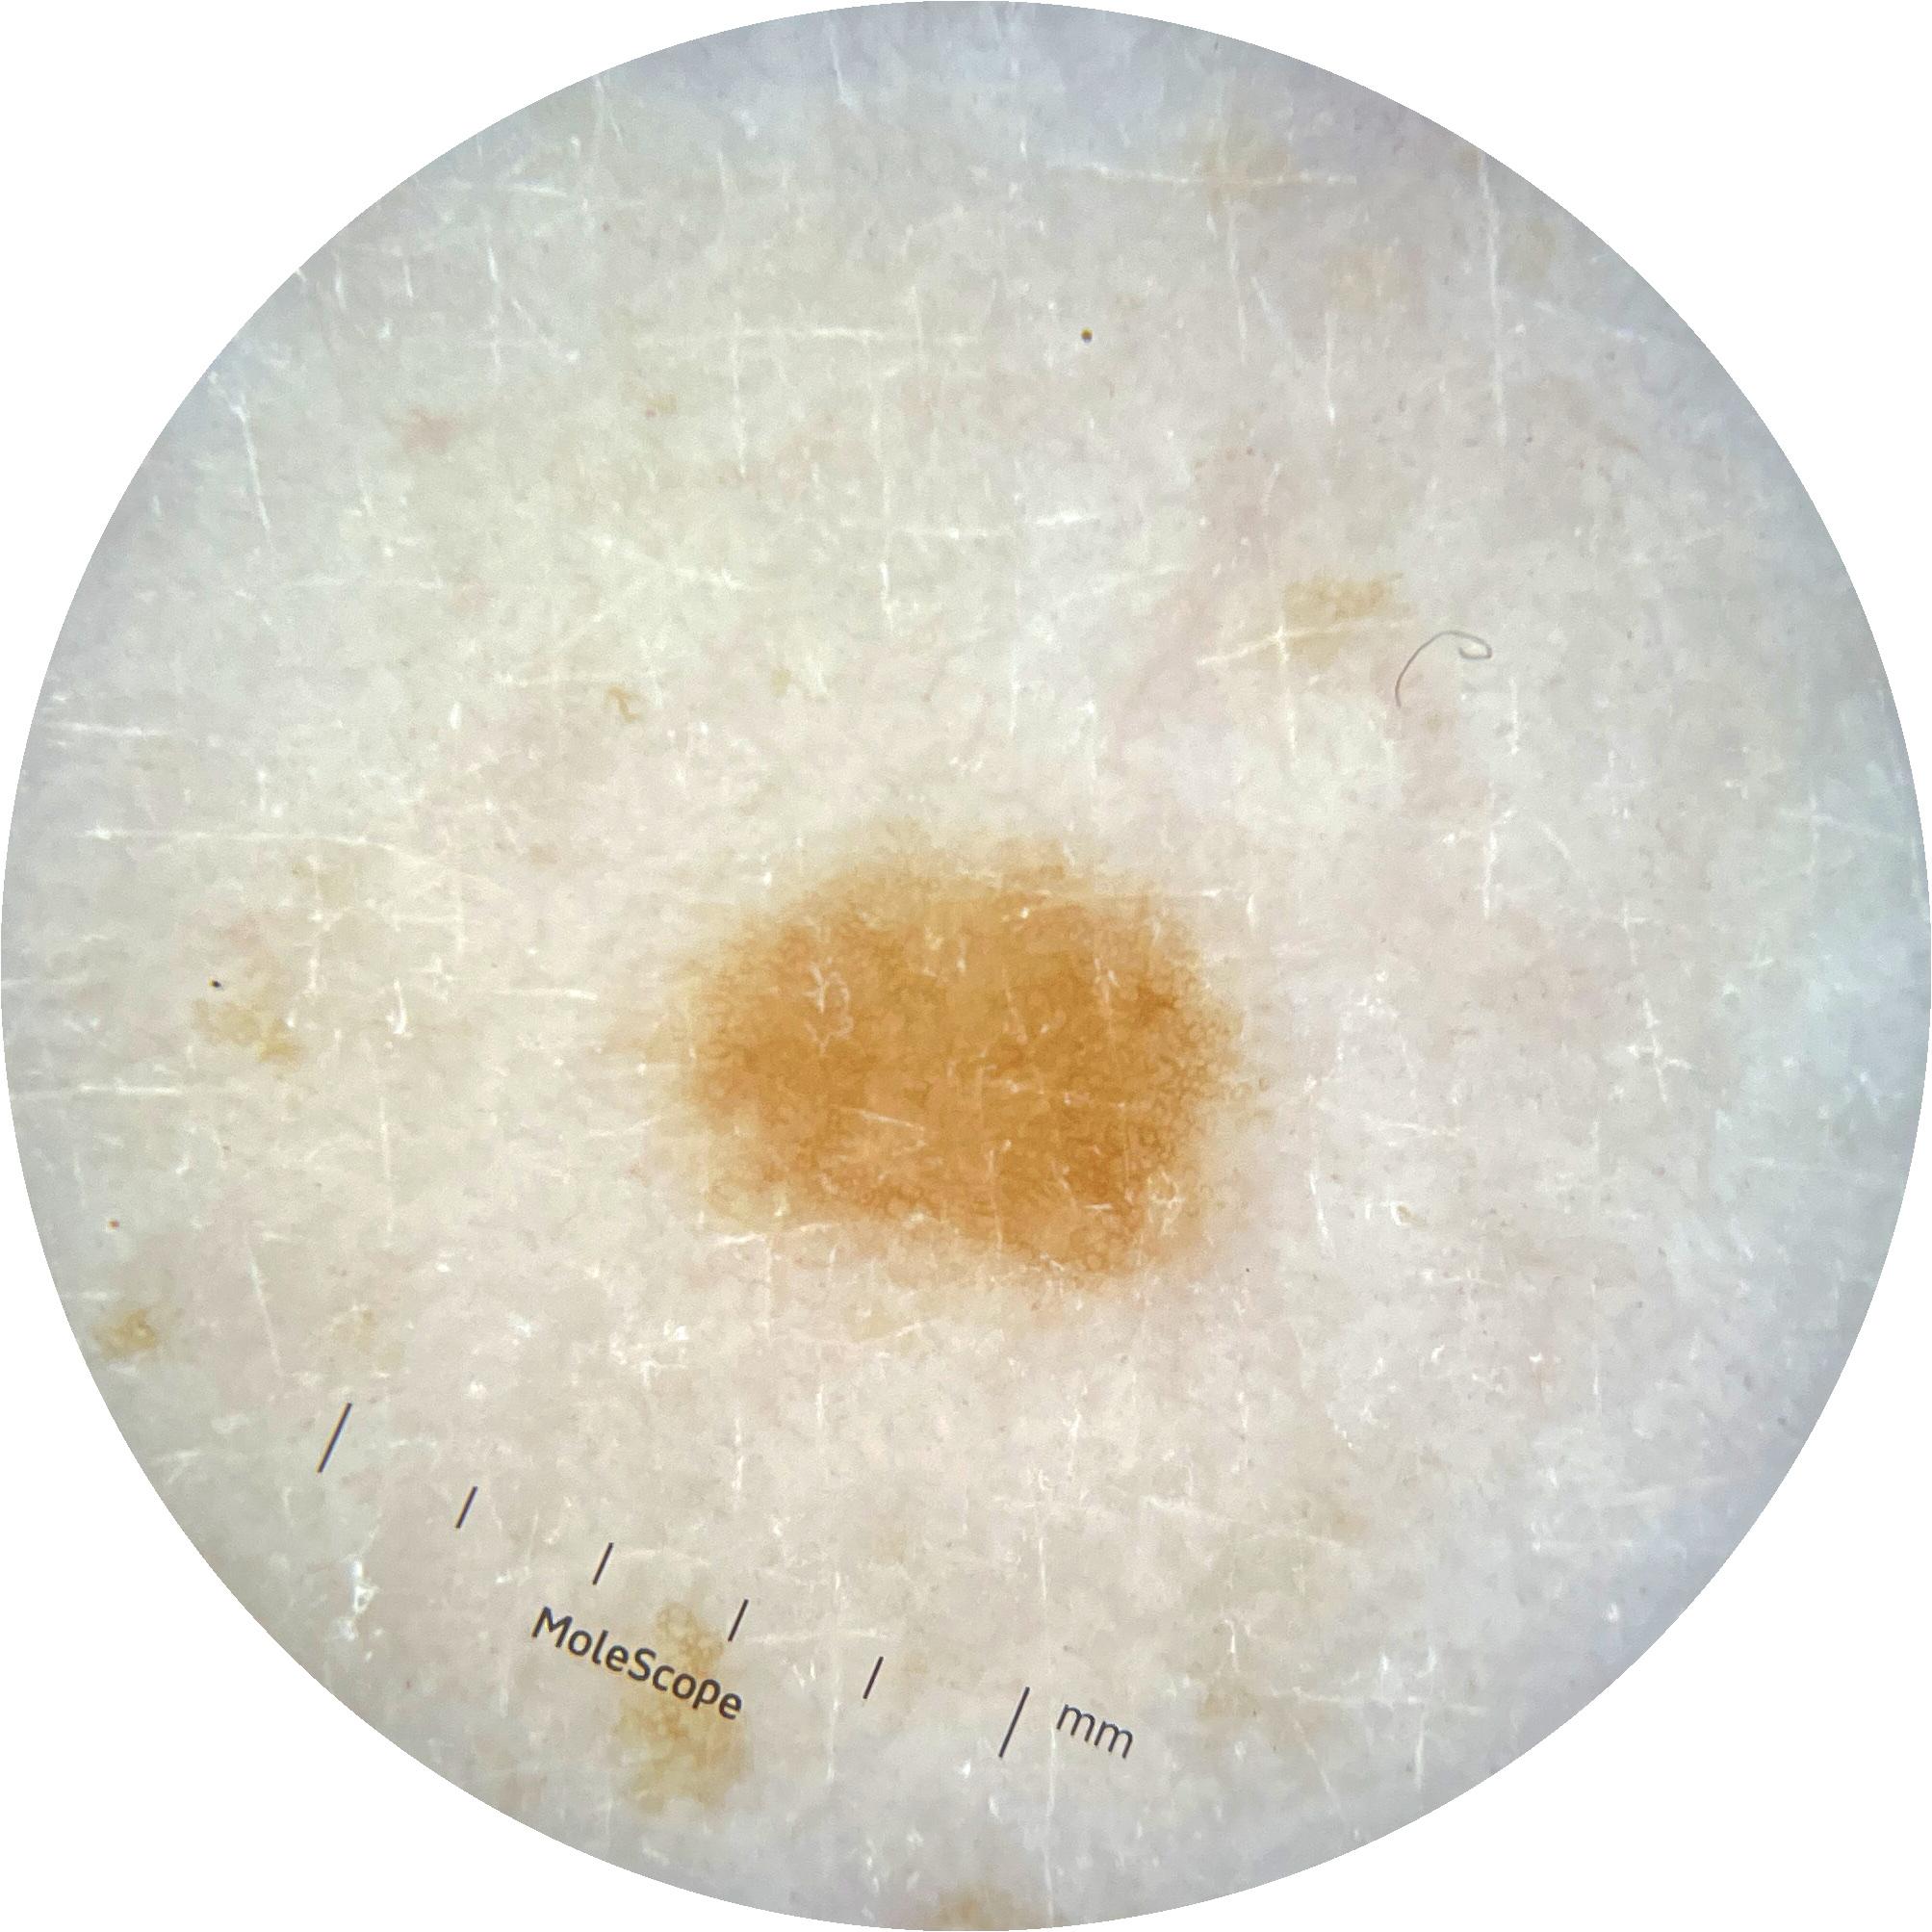

ISIC_9785574

image_type dermoscopic

lesion_id IL_0236417